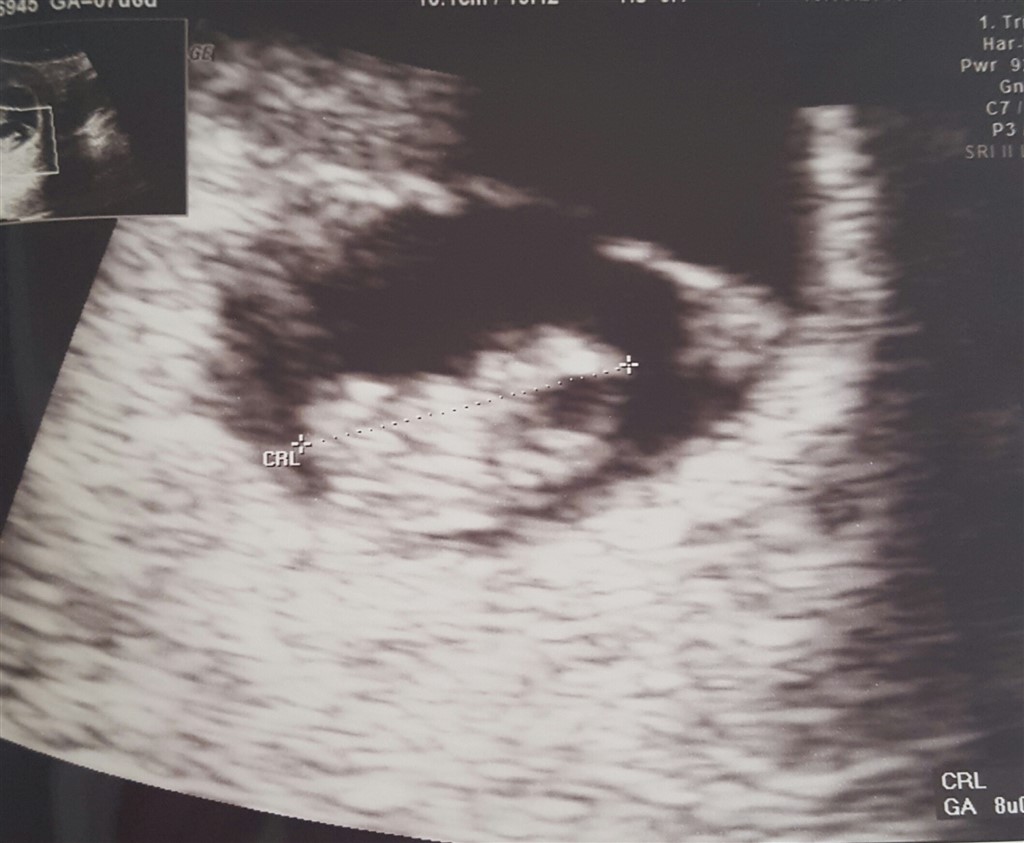

jeg er noget spændt på hvad der gemmer sig der inde. Og om det ligger rigtigt, som det selvfølgelig gør

Vi har fået tilbud scanning af klinikken, men det ligger i vores ferie, så må heller få booket en tid inden længe.

Bliver så sjovt at se hvor mange der gemmer sig